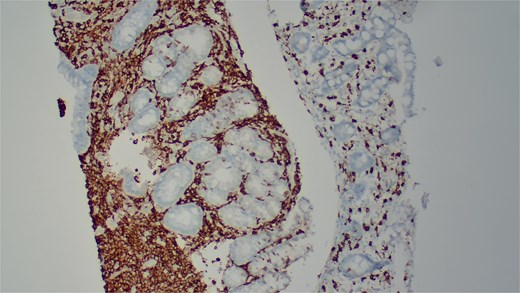

She underwent an EGD, which demonstrated mild chronic duodenitis and erythematous gastric mucosa. Biopsies were obtained from the gastric body, antrum, and duodenum. Histopathological examination revealed abnormal mast cell proliferation in the duodenum (Fig. 1), confirmed by positive staining for CD117 and tryptase, with aberrant CD25 expression (Fig. 2). The gastric mucosa exhibited focal intestinal metaplasia, though no dysplasia was noted. Molecular analysis identified C-KIT D816V mutation. Given these findings, serum tryptase levels were obtained, and additional hematologic evaluation was recommended to assess systemic involvement. The patient was referred to hematology for further assessment of potential bone marrow involvement and systemic treatment options.

Immunohistochemical staining demonstrates positive expression of CD117.